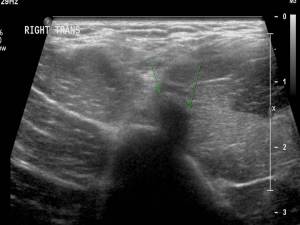

In his review of the evidence and in the presentation of several case studies, Dr. Finnoff made a compelling argument for the power of this modality to enhance interventions we offer our patients.

Regarding the diagnostic capabilities of point-of care sports ultrasound, he emphasized the power of having a dynamic imaging modality as opposed to a static one. MRI is a powerful tool we sports physicians use frequently, but it generates static images. Ultrasound can much more readily demonstrate a subluxing peroneal tendon, for instance, or (in a case study Dr. Finnoff presented) demonstrate that not all snapping hips are attributable to the iliopsoas or tensor fascia latae. Furthermore, ultrasound is much cheaper and more portable than MRI. And concerns over patient claustrophobia or implanted shunts are no longer concerns when ultrasound is employed, not to mention the superior safety profile of ultrasound compared with imaging relying on ionizing radiation (e.g. CT scan and plain films).

‘Think so’ vs. ‘Know so’: I’ll end with a story Dr. Finnoff showed in his talk. One of his published works, cited in the position statement, describes work he did with a colleague on ultrasound- vs. fluroscopic-guided piriformis injection. On his arrival at the Mayo Clinic, he got into a friendly debate with a colleague who, when performing the latter procedure, ‘knew’ he was in the right place. Dr. Finnoff demurred, and so the two did a cadaveric study comparing the success rate of the two procedures. This published study demonstrated that piriformis injections done under fluroscopy were accurate only 15% of the time, whereas those done under ultrasound guidance were 95% accurate!